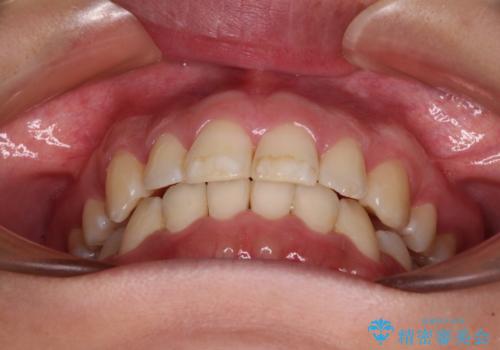

- 上下前歯のデコボコを気にして来院された患者様です。

デコボコが強いため、非抜歯で矯正をすると出っ歯仕上がりとなるため、上下左右の第一小臼歯4本を抜歯することとしました。

当初予定は2年半程度と伝えていましたが、2年にも満たない期間で治療を終えることができました。